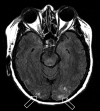

Fig 2.

Patient 21 is a 59-year-old woman who developed altered mental status, loss of consciousness, and severe hypertension (220/100 mm Hg) 17 months after cadaveric renal transplant for hypertension-related chronic renal failure. She was being managed for mild organ rejection just before toxicity. MR imaging (FLAIR sequence) obtained at toxicity demonstrates primarily cortical vasogenic edema in the occipital poles bilaterally (open arrows) judged Edema grade 1. Follow-up MR imaging 3 days later demonstrated resolution of the vasogenic edema.